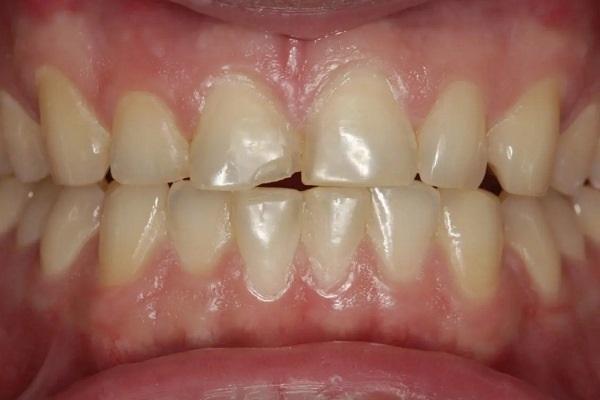

А как насчет выравнивания зубов-антагонистов? На режущих краях зубов 31 и 41 (фото 2) наблюдался чрезмерный износ. Со стороны резцов был виден значительный износ всех краев нижней челюсти из-за окклюзионного заболевания, которое часто наблюдается, но не лечится (фото 3). Также зуб 41 располагался на лицевой стороне таким образом, что при выступающей экскурсии он преждевременно соприкасался с небной поверхностью зуба 11, создавая дополнительную нагрузку как на небную поверхность, так и на резцовый край зуба 11, прежде чем соединиться с остальной частью переднего сегмента верхней челюсти. Это демонстрирует, что решение этих проблем реставрационными методами включает в себя нечто большее, чем просто исправление сколов композитной реставрации.

Фото 2: Зубы выступают вперед, что свидетельствует о чрезмерном износе зуба (41), расположенного напротив зуба 11, что указывает на гиперфункцию и повышенную функциональную нагрузку на восстановленную область.